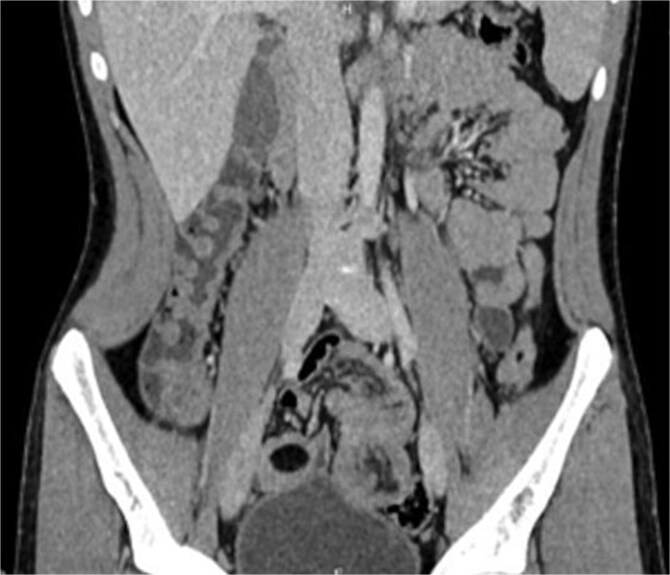

肠套叠是一种罕见的成人小肠梗阻的原因,通常与恶性病变有关,但偶尔由良性病因如脂肪瘤引起。临床表现多样,症状从腹痛到排便习惯改变。计算机断层扫描在诊断中起着关键作用。手术干预仍然是治疗的基石,包括切除受影响的肠段和去除潜在的病变。本病例报告报告了一例27岁男性空肠脂肪瘤引起的肠套叠的独特病例,重点介绍了其临床特征、诊断方法以及及时手术干预对患者最佳预后的关键作用。

Intussusception is a rare cause of adult small bowel obstruction, often associated with malignant lesions but occasionally caused by benign etiologies like lipomas. The clinical presentation is diverse, with symptoms ranging from abdominal pain to changes in bowel habits. Computed tomography plays a pivotal role in diagnosis. Surgical intervention remains the cornerstone of treatment, involving resection of the affected bowel segment and removal of underlying lesions. This case report presents a unique occurrence of intussusception caused by jejunal lipoma in a 27-year-old male, highlighting its clinical features, diagnostic approach, and the crucial role of timely surgical intervention for optimal patient outcomes.